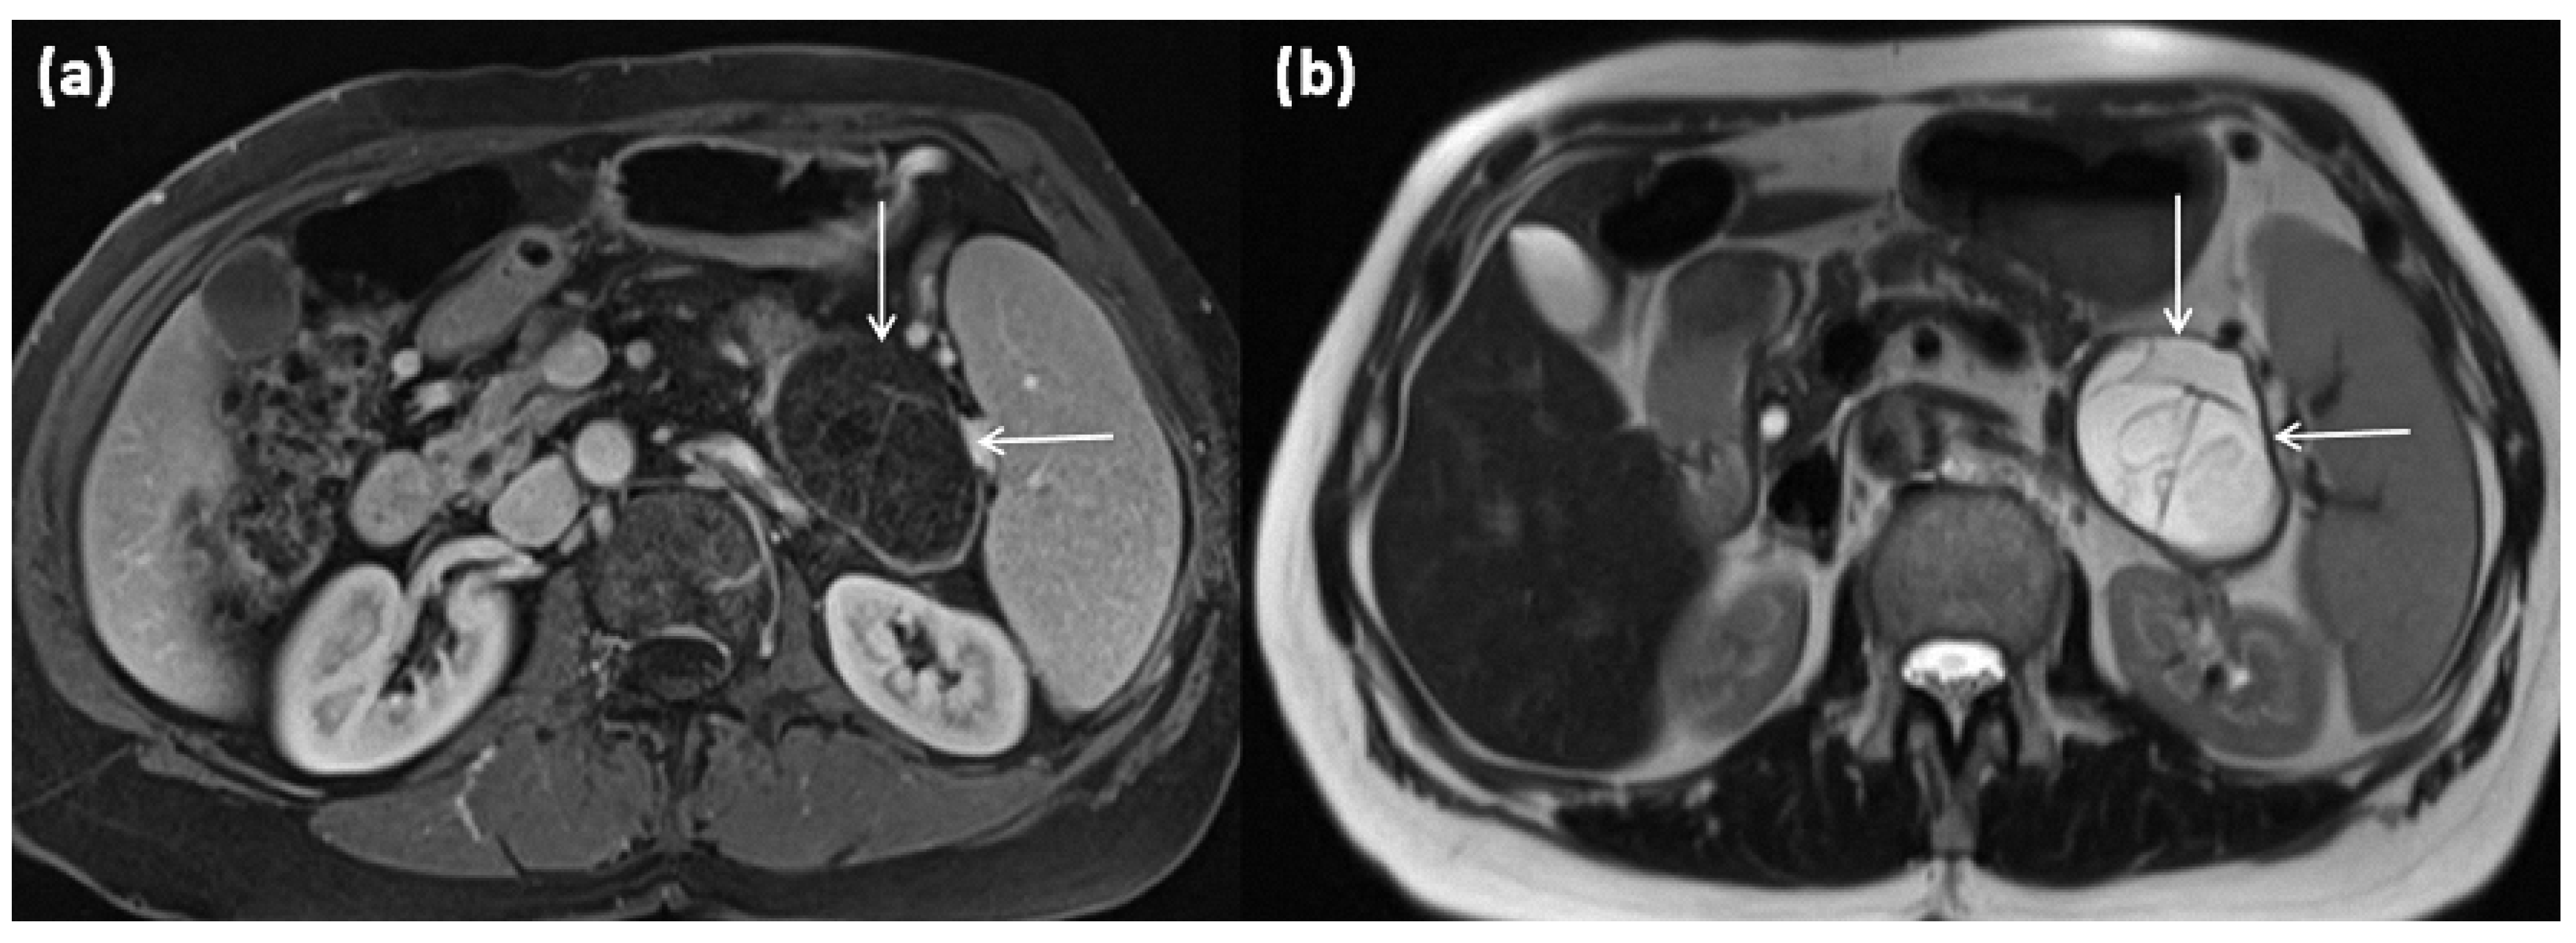

3.2. Macrocystic Tumors: Mucinous Cystic Neoplasms (MCN)

3.3. Microcystic Tumors: Serous Cystic Neoplasms (SCN)